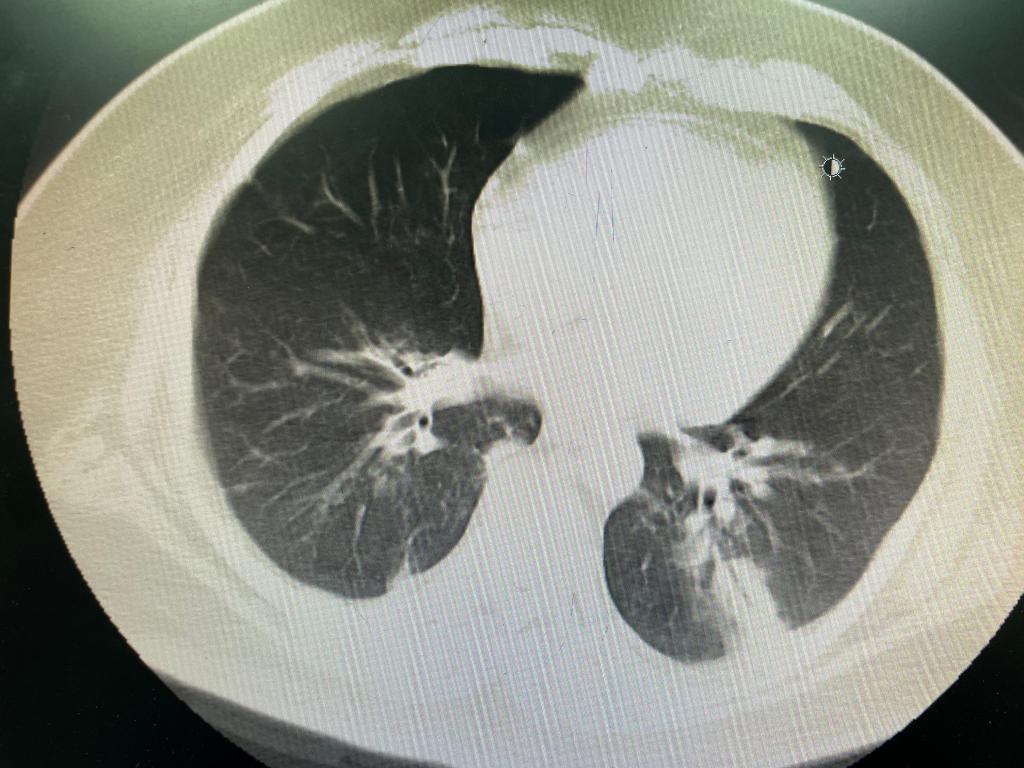

图5 ECMO下机后复查CT